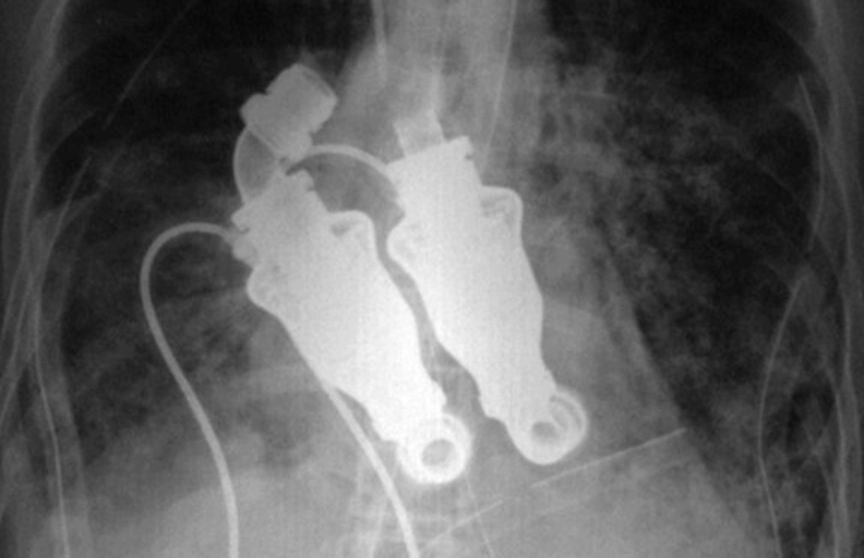

На рынке сейчас огромный выбор желудочковых вспомогательных аппаратов, способных помочь больному человеческому сердцу. Сердце же Льюиса было повреждено до такой степени, что ни один имплантат уже не облегчил бы его мучения. Даже о пересадке донорского органа никто не заикался, ведь амилоидоз - это тотальное нарушение обмена веществ, которое рано или поздно уничтожило бы и донорское сердце. Но доктору Фрейзеру с коллегами удалось найти решение. Для этого за основу они взяли пару LVAD (L - означает "левый", эта турбинка производится как имплантат, ассистирующий левому желудочку сердца) и модернизировали их таким образом, чтобы, будучи соединенными вместе, они смогли бы заменить сердце Льюиса целиком.

Искусственное сердце было меньше, дешевле, долговечнее, надежнее и безопаснее. Ведь оно не перекачивало кровь, в отличие от своих предшественников, а благодаря вращающимся частям поддерживало постоянную циркуляцию крови. Это не только продлевало срок службы искусственного органа, но и сильно снижало риск образования сгустков крови, что являлось серьезной проблемой предыдущих имплантатов.